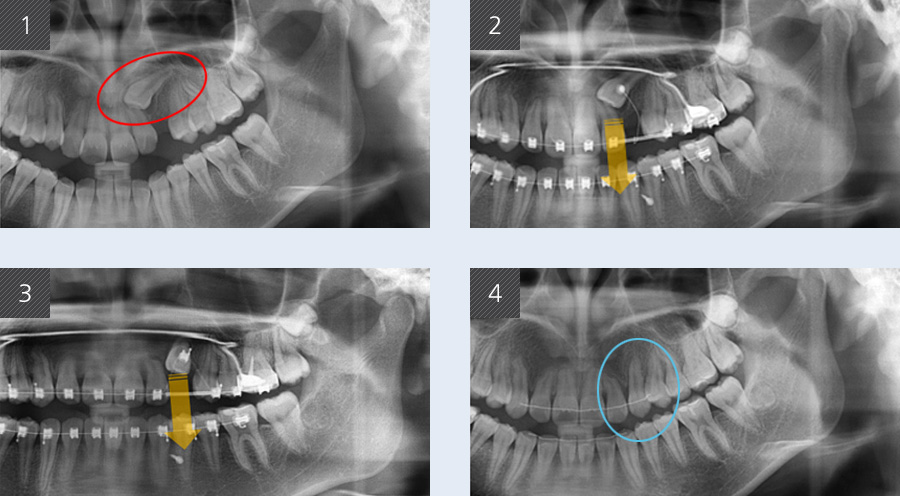

앞니가 고르지 않고 송곳니가 나지 않는 증상으로 내원한 12세 여학생입니다. 환자의 좌측 위 송곳니가 수평으로

매복되어 있었고 이로 인해 주변 치아 차이가 벌어진 상태였습니다. 발치를 하여 치료 기간을 줄이는 방법 대신,

자연치아를 유지할 수 있도록 간단한 수술을 통해 매복 치아에 치아교정 장치 부착하고 아래 쪽에는 교정용

스크류를 식립하여 치료를 진행하였습니다.

본래 송곳니가 있어야 할 자리로 매복된 송곳니를 이동시켰습니다. 그 결과 고르지 않았던 앞니가 가지런해졌으며

치아 사이에 공간이 생겼던 곳에 송곳니가 정상적으로 위치하게 되었습니다.